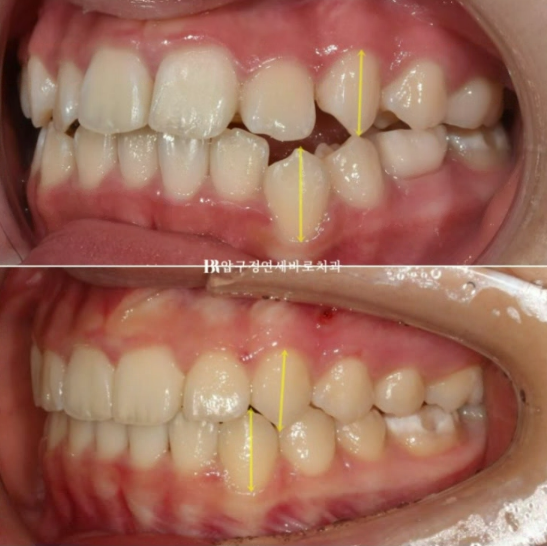

약 7개월에 걸쳐 첫번째 세트를 모두 낀 후의 모습입니다.

24.03

이미 한쪽으로 쏠려버린 중심선을 얼굴 및 인중과 맞추는 교정은 간단해 보이지만 간단하지 않습니다.

어금니의 문제가 앞니까지 이어온 것이므로 한쪽 어금니 전체의 이동이 수반이 되어야 합니다.

왼쪽 위 어금니를 앞으로 끌어오기 위해서 잇몸에 교정용 미니스크류도 심고 뺏다꼈다 하는 고무줄도 쓰면서 진행했습니다.

재제작 후 추가장치에서는 작은어금니를 뿌리까지 평행하게 땡겨오기 위한 장치가 추가되었습니다.